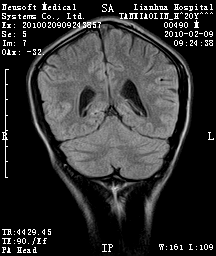

20岁男性患者,平时偶有头痛而无其他不适,现因持续头痛服药后无缓解而来院就诊。

松果体囊肿?

松果体区占位继发轻度脑积水?该患者有ct资料,我已发上。

考虑松果体囊肿。